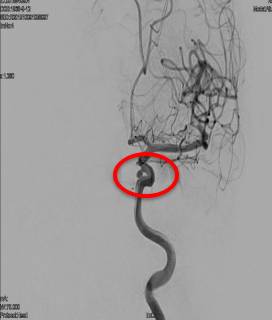

DSA:基底动脉尖端分叶状小动脉瘤,左侧颈内动脉床突上段动脉瘤。

基底动脉尖1.8mmx3.2mm囊性显影,分叶状动脉瘤。